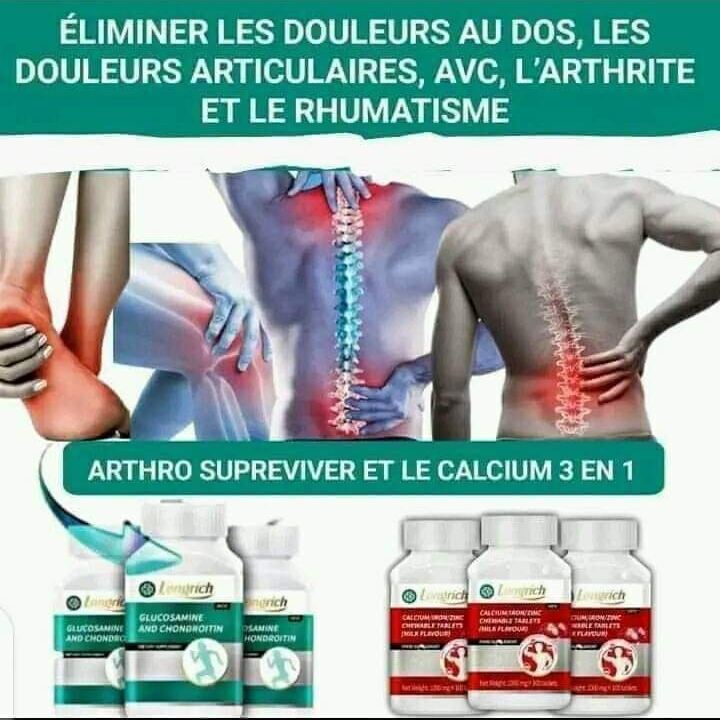

Complement alimentaire arthro et calcium

Complement alimentaire agissant dans vos cellules afin de guérir les maladies liés aux os. Peu importe le problème, un accident, la vieillesse et autres nous pourrons vous apporter satisfaction Ces compléments alimentaires vous redonne de l'énergie, comble vos manquements ou carences et éliminent les risques d'AVC